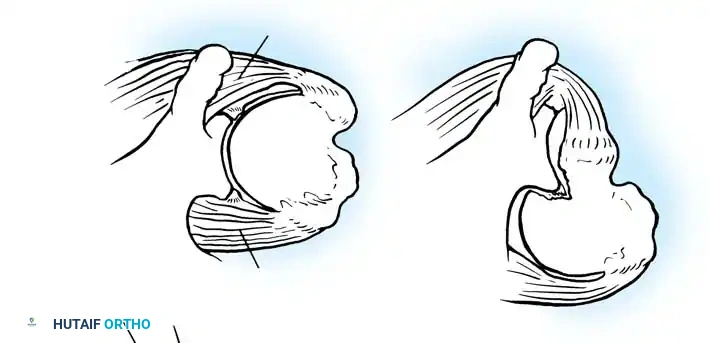

- Inferior Glenohumeral Ligament (IGHL) Complex: The most critical static stabilizer. It attaches to the glenoid margin from the 2-o’clock to 3-o’clock positions anteriorly, extending to the 8-o’clock to 9-o’clock positions posteriorly. Its humeral attachment lies below the articular margin on the anatomical and surgical neck. O’Brien et al. described this complex as a "hammock-like" structure consisting of a thickened anterior band, a posterior band, and a thinner axillary pouch.

CLINICAL PEARL: The biomechanics of the IGHL complex are dynamic. With external rotation and abduction, the hammock shifts anteriorly and superiorly; the anterior band tightens to prevent anterior translation, while the posterior band fans out. Conversely, internal rotation tightens the posterior band. The anteroinferior band is the primary restraint to anterior translation at 90 degrees of abduction and external rotation (the classic apprehension position).

Turkel et al. demonstrated that true anterior dislocation cannot occur if the IGHL remains intact. Furthermore, Warren introduced the "circle concept," proving that for significant anterior translation to occur, there must be concomitant disruption or plastic deformation of the posterior capsular structures.

The Bankart Lesion and Capsular Failure

In 1906, Perthes first described the detachment of the anteroinferior labrum. In 1938, Bankart popularized the concept, describing the traumatic detachment of the fibrocartilaginous labrum and anterior capsule from the glenoid rim—now universally known as the Bankart lesion. Rowe et al. identified Bankart lesions in 85% of traumatic recurrent dislocations.